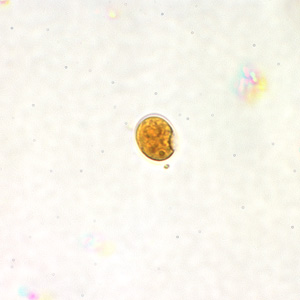

E.nana cysts

four nuclei. centrally karyosome only visible in trichrome stain